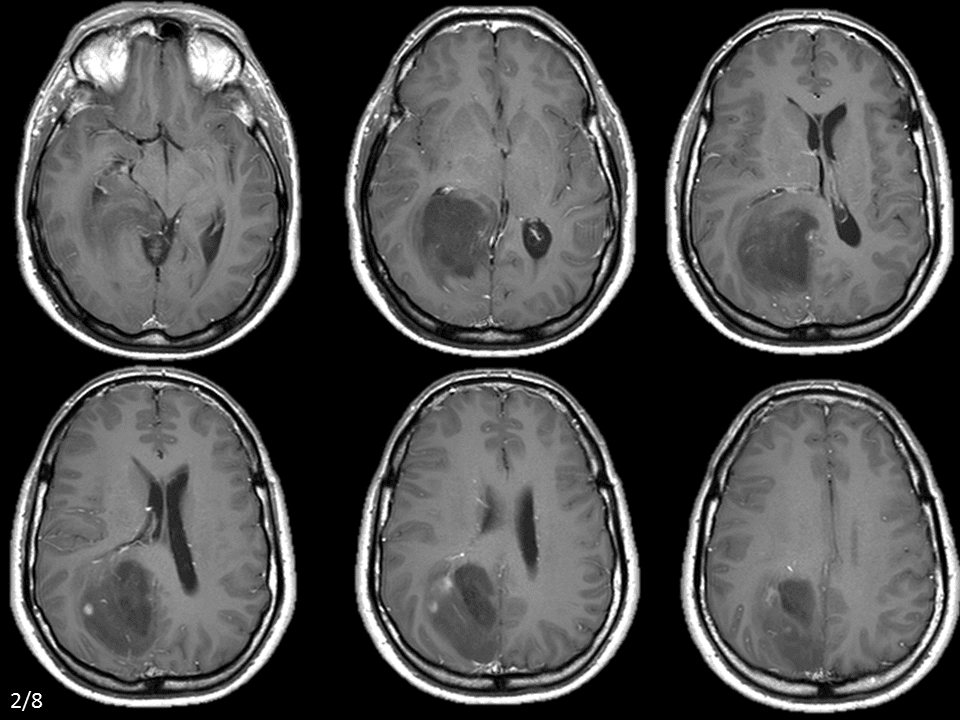

U tế bào hình sao

» Thông tin: Nam giới – 42 tuổi.

» Lâm sàng: Đau đầu.

# U sao bào kém biệt hóa (Anaplastic Astrocytoma)